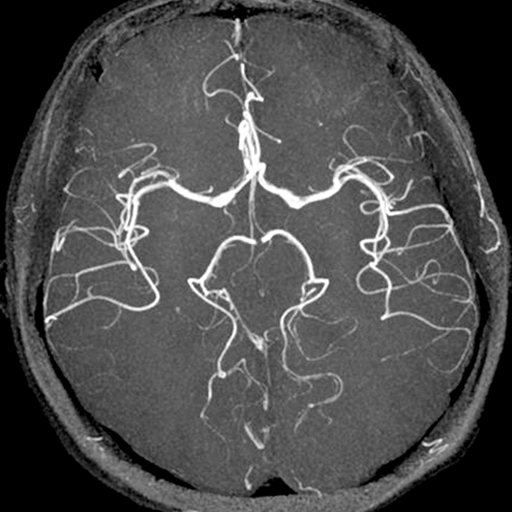

MRAとは、磁気の力を利用して血管の状態調べる検査です。頭部のMRAでは、脳の血管だけに特化して病変の有無を確認します。くも膜下出血の原因となる脳動脈瘤のスクリーニング検査として有用であり、脳血管の閉塞や狭窄、未破裂椎骨動脈解離、脳血管奇形などを検出します。MRAは磁場による血流の信号を画像化しています。磁場が弱く画像の不鮮明な場合、擬態的に病巣(動脈瘤、狭窄等)に見えてしまうようなことが生じることがあります。しかし、磁場強度を3.0テスラに上昇させると高分解能を有する画像が得られ、細かいところがよく見えるようになり、病変の診断能力が著明に向上します。(そのため当院では頭部検査に3.0テスラMRIを推奨しています。)

頭部領域の検査は、脳血管の診断能が顕著に向上している3.0テスラMRIにて検査を行います。